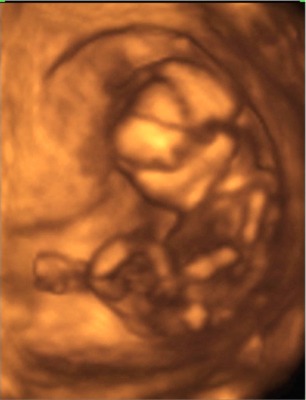

Megjöttünk a 4D-ről :) :) :)

Nagyon nagyon jó volt! Csúcsszuper :D

A babucim iszonyú jól érzi magát odabent, fészkelődik, rugdalózik megállás nélkül, ugyanúgy mint a 12 hetesen :lol:

Fejétől a lábujjáig 13cm .. persze ennél kisebb helyet foglal, mert fel van húzva a lába ..stb.

10,2 dkg a Lelkem :)

Láttuk a kis szívét, a 4 szívkamrát, az agyát... az agyféltekéket, a gyomrát, a húgyhólyagját .. szóval messze felülmúlta a vizsgálat minden várakozásunkat.

A csöppség nemét nem merték biztosra mondani, így ezzel kapcsolatban még izgulhatunk kicsit :lol: :lol:

A 2D alapján kislányt mondanának .. de a 4D-n néha láttunk gyanus elemeket. De az lehetett a szeméremajkak is .. mert ebben az időszakban még azok is csúcsosak :) nah majd kiderül időben :) A nő szerint ebben az időszakban még nem lehet 100%-osra mondani, ő nem szeret jósolgatni.

A pici hasamnak viszont megvan az oka .. a hátrahajló méhem egy dolog, de abban is leghátul, lent a medencémben fészkelte be magát a babuci, így egészen a szeméremcsontomhoz kellett bekukkantanunk .. és nagyon nehezen tudtuk őt követni. De szerencsére egyfolytában mozgott .. így mindenét meg tudtuk nézni, és elkaptunk nagyon jó pillanatokat!

A kiskönyvemben április 9re vagyok kiírva, ha a hosszú ciklust belekalkulálom, akkor április 13. Na az első UH-n április 19-et mondtak (ez 8 hetesen volt), aztán a 12 hetesen április 13-at, most pedig április 14-et :) :) Nagy különbségek nincsenek, így rendben fejlődik a Drága!!!!

Boldogság van!!!

Mindjárt megpróbálok fotót mutatni róla!

Kép \"mutatom az arcocskám\"

Kép \"vakarom a fejecském\"

Kép \"látjátok hogy tornázom?\"

Kép \"elfáradtam ... hátrabújok pihenni\"